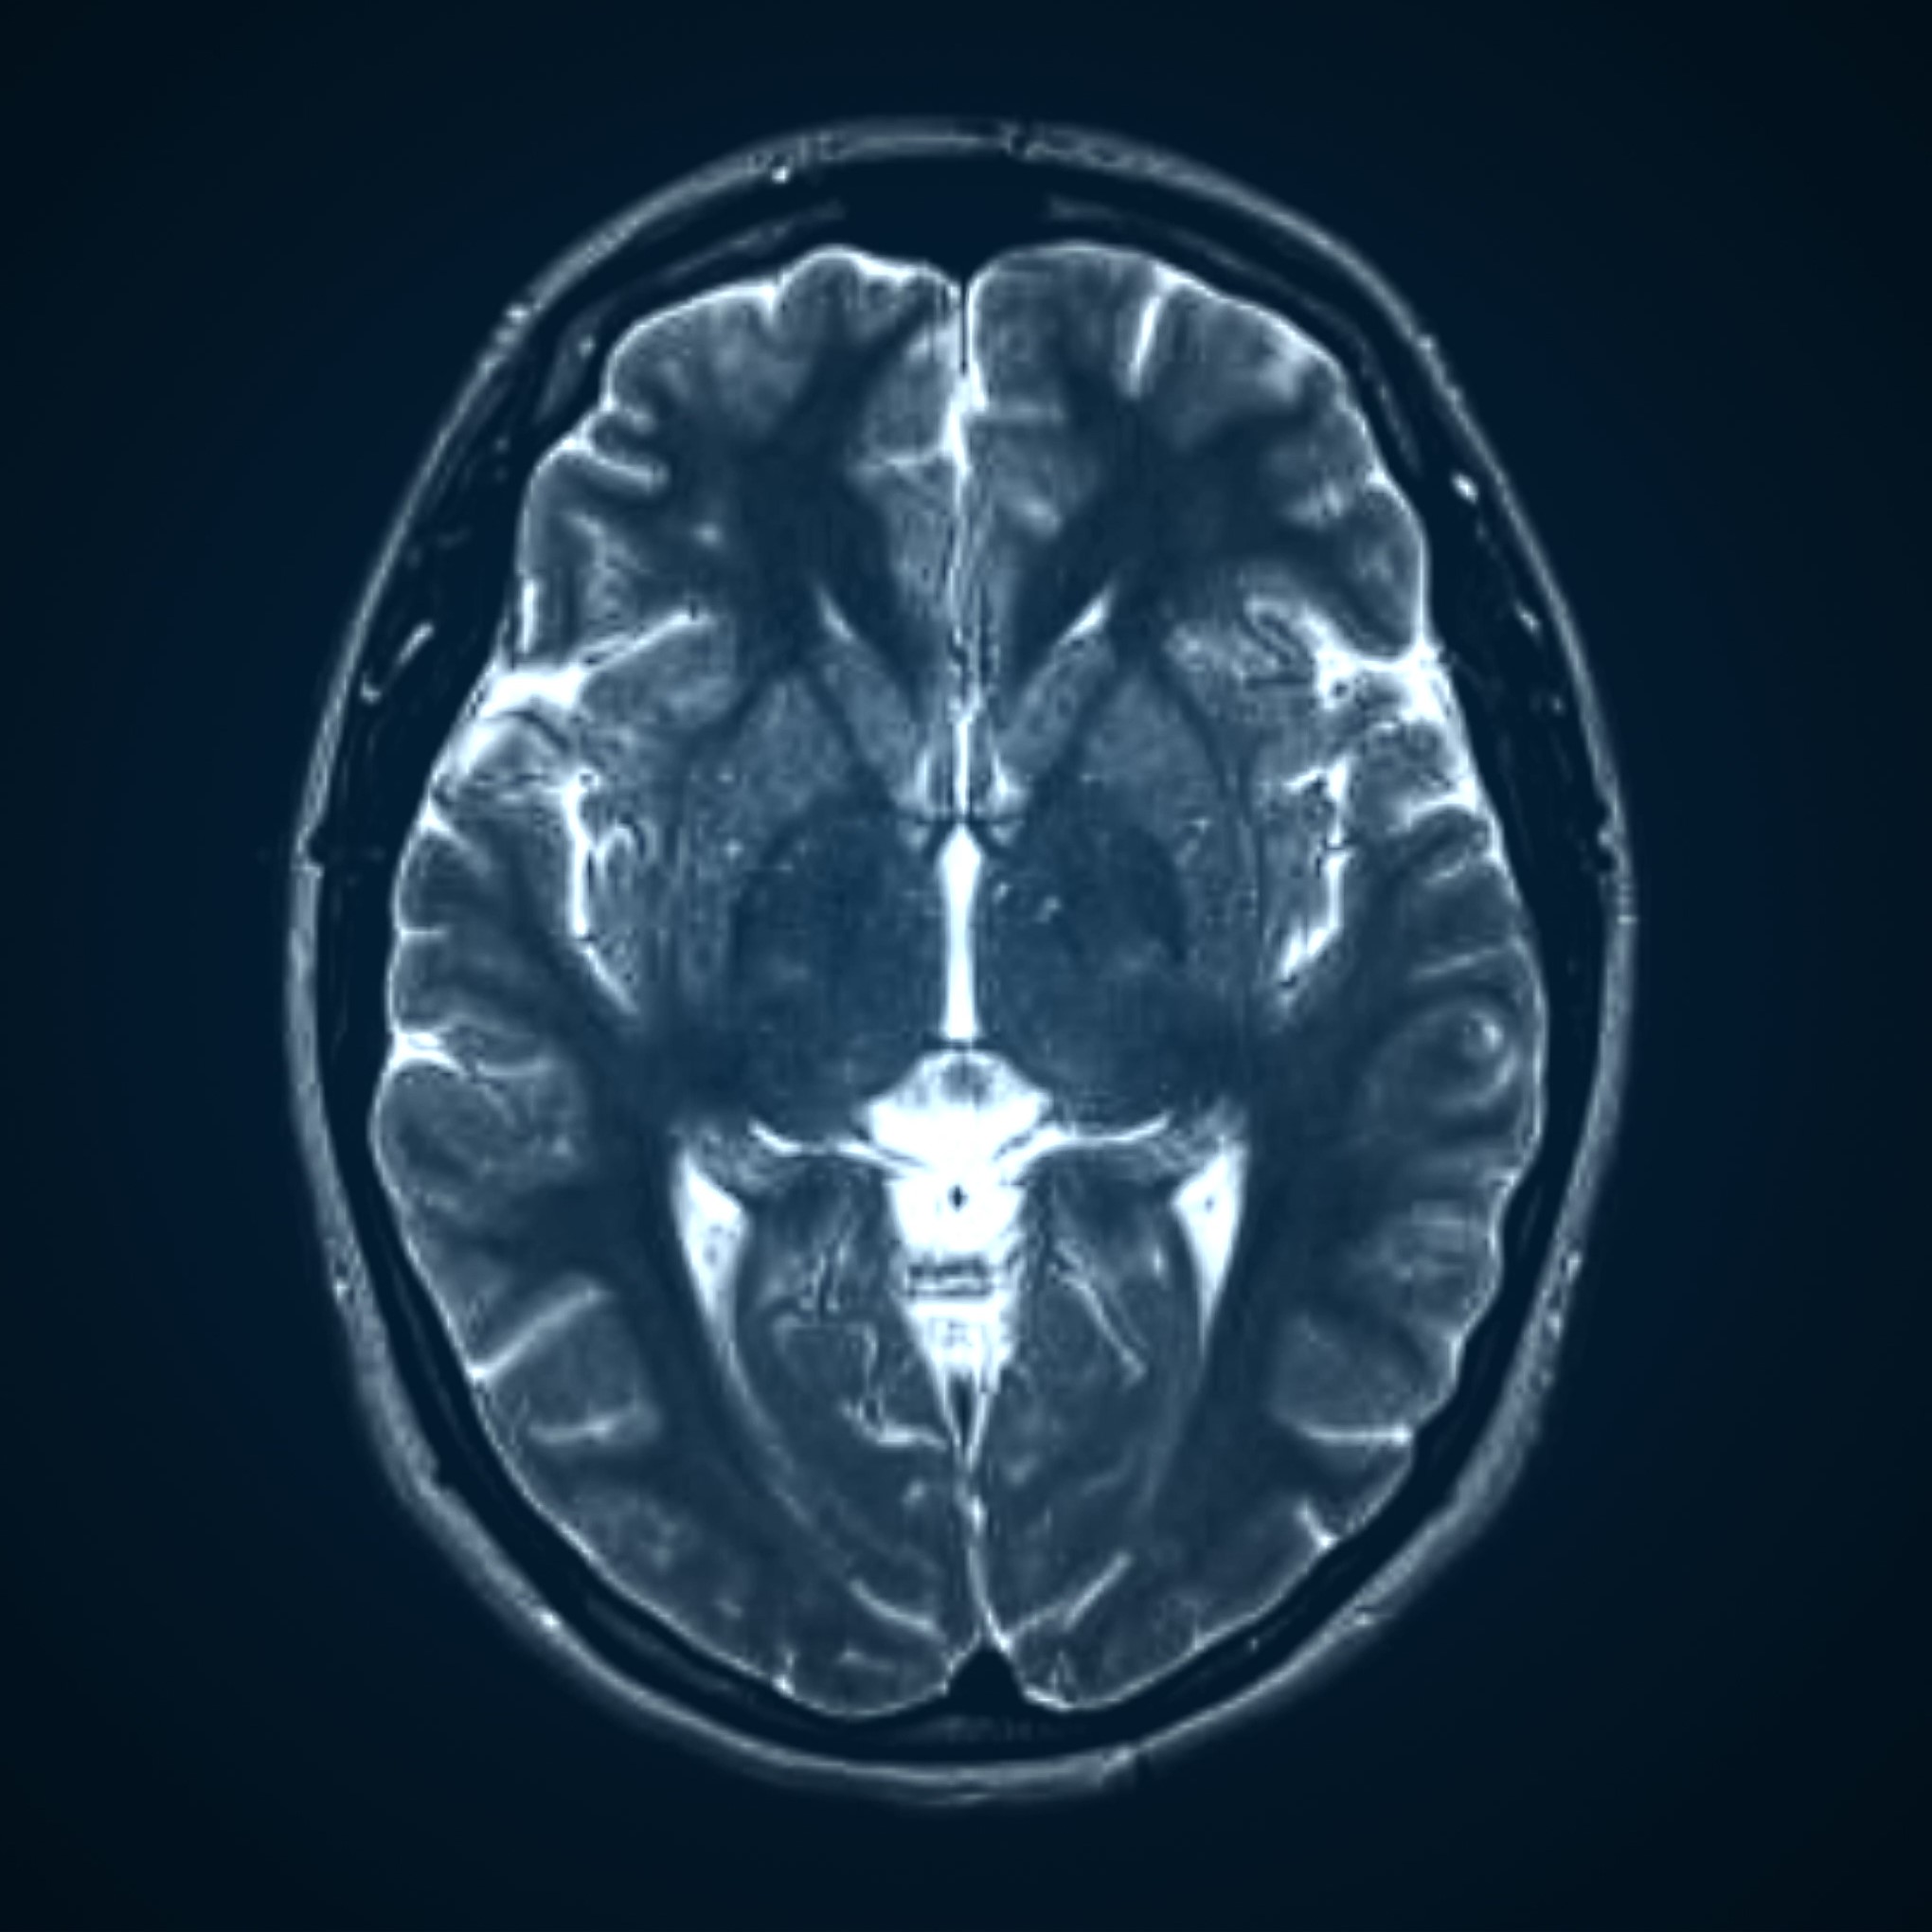

Tumor Detector

Using the PyTorch,timm, matplotlib, and numpy libraries, I made a ML program that detects gliomas, meningioma, and pituitary tumors in MRI scans. This program trains the model using over 5000 images. I presented this at the STEAM @ Schoolcraft conference, showing how AI is used to positively impact the medical field and received first place for my work.

Tumor Detection